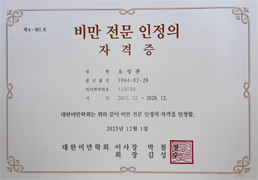

비만통증클리닉

비만통증클리닉

체형 진단 및 운동치료

- 비만통증클리닉

- 체형진단 및 운동치료